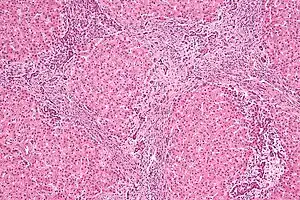

| Micrograph of focal nodular hyperplasia. H&E stain. | |

Focal nodular hyperplasia's most recognizable gross feature is a central stellate scar seen in 60–70% of cases. Microscopically, a lobular proliferation of bland-appearing hepatocytes with a bile ductular proliferation and malformed vessels within the fibrous scar is the most common pattern. Other patterns include telangiectatic, hyperplastic-adenomatous, and lesions with focal large-cell dysplasia.[4] Rarely, these lesions may be multiple or can occur as part of a syndrome with hemangiomas, epithelioid hemangioendothelioma, hepatic adenomas, fibrolamellar hepatocellular carcinoma, vascular malformations of the brain, meningiomas, and/or astrocytomas.[4]